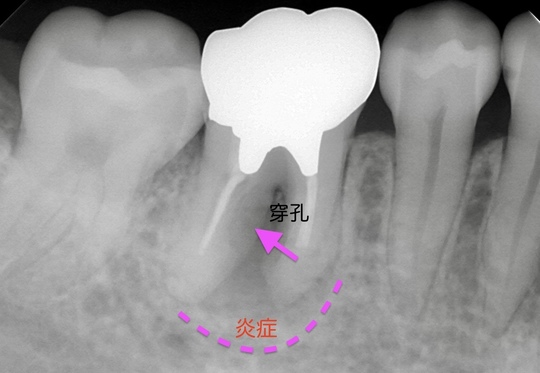

自費根管治療症例2 治療前

左下の奥歯が根の治療を受けているが治らない。

管の分かれている部分に根の治療による穿孔がありました

穿孔部分の封鎖と通常の根管治療を行いました

症状は、完全に消えて、穿孔部分の封鎖と確実な清掃、充填が確認できます